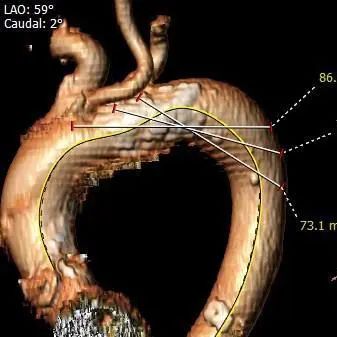

外周血管及主动脉弓解剖

瓦氏窦、窦管交界及升主动脉整体内径较小;左右交界及左冠窦上方升主动脉壁有一长条型严重钙化,延近小弯侧延申至升主动脉。

入路血管钙化严重,弓部、腹主动脉起始段及髂动脉分叉前后钙化极重,多处环状及近环状钙化,双侧血管内径尚可。